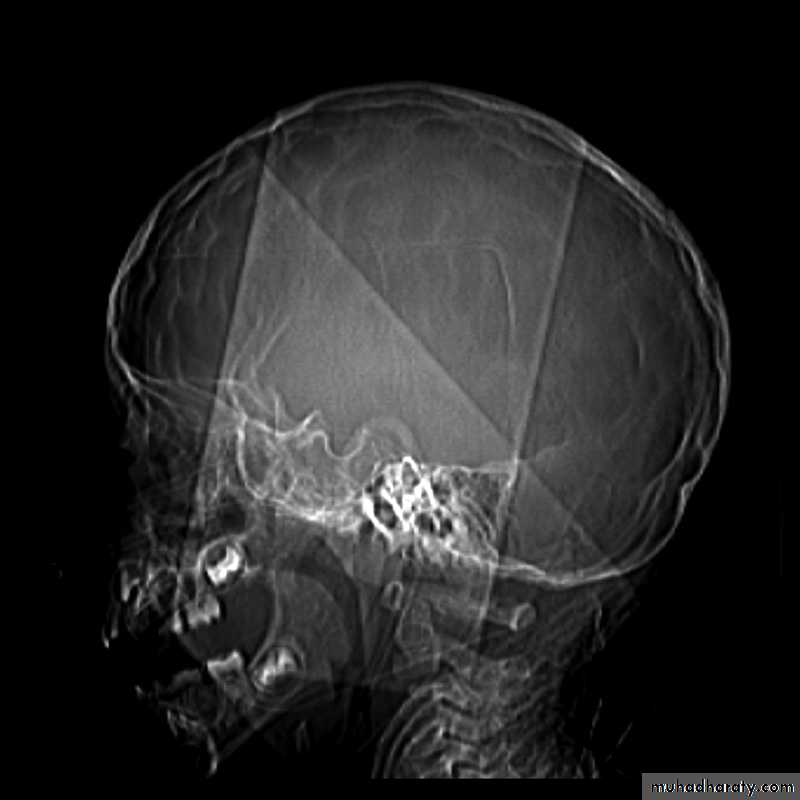

Skull X-ray findings in increased intracranial pressure

• Sutural separation in children.• ‘Copper-beating’ marking of the cranial vault.

• Thinning of dorsum sellae.

• Erosion of the posterior clinoid process.

Copper-beating’ marking